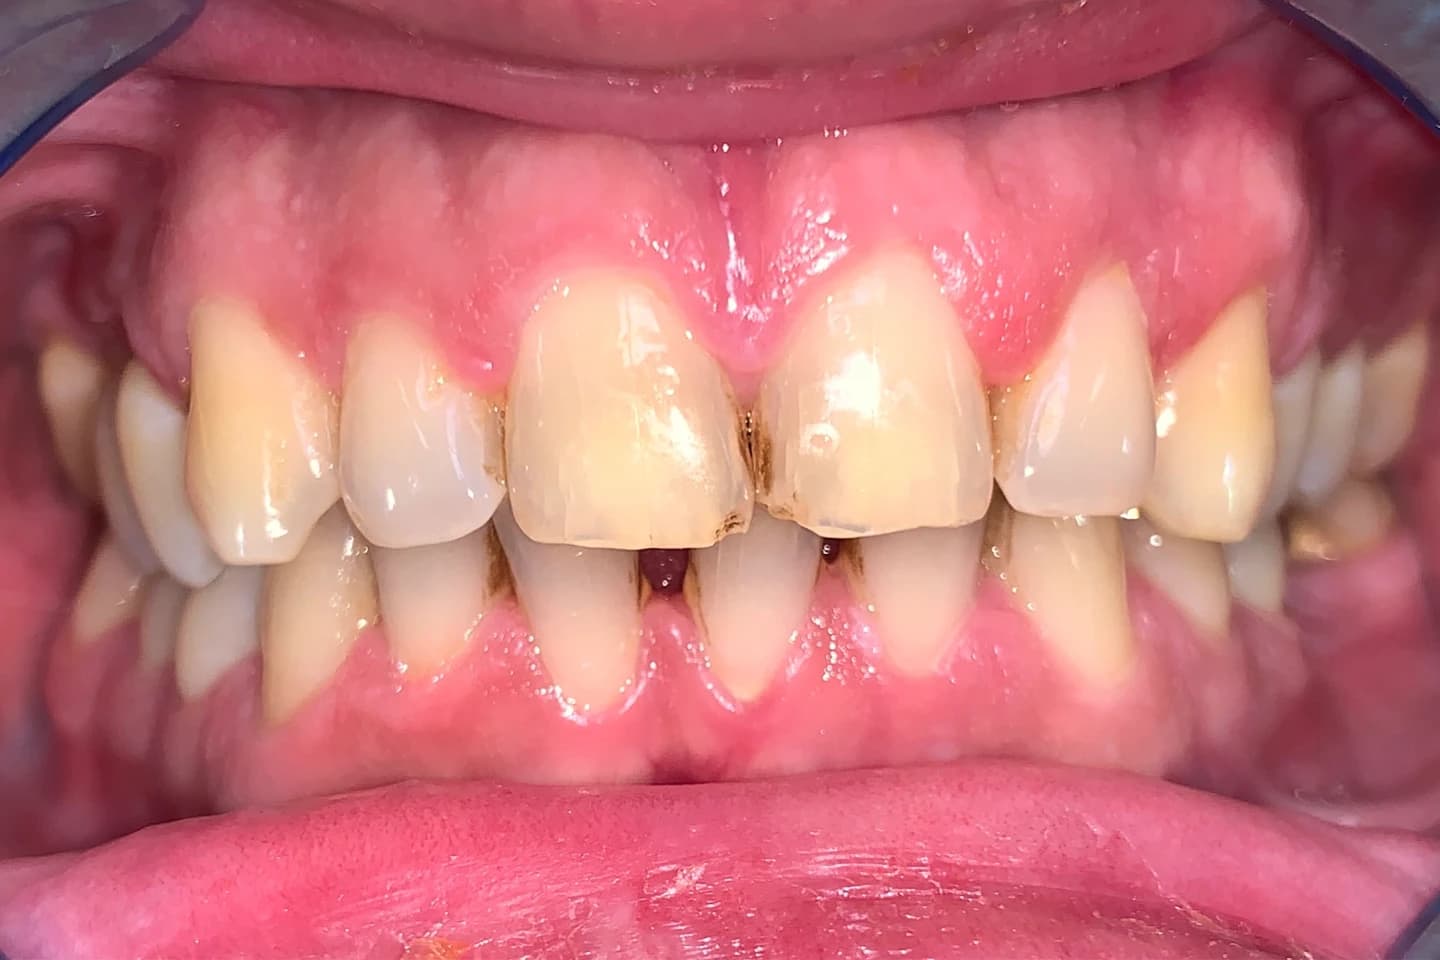

Implanti - pre i posle

- Pogledajte kako smo pacijentima sa nedostatkom zuba vratili samopouzdanje i funkcionalnost uz pomoć zubnih implantata. Naši radovi jasno pokazuju kako implanti mogu da transformišu vaš osmeh i poboljšaju kvalitet života.